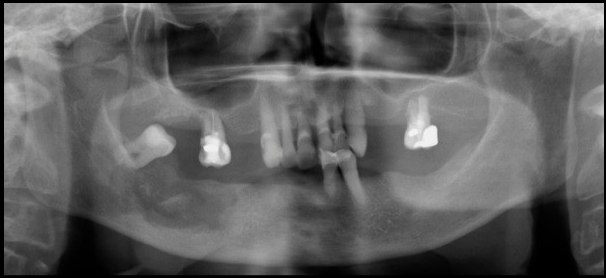

Paciente femenino 72 años de edad, acude a la consulta por presentar secresión purulenta en zona de extracción de pieza 4.6 realizada hace aproximadamente cuatro meses . En la radiografía panorámica se observa rarefacción ósea que compromete cuerpo mandibular del lado derecho con aumento de la densidad ósea circundante; en las radiografías intraorales apreciamos reacción periostal a nivel de la tabla ósea vestibular, así como la presencia de secuestro óseo hacia la tabla ósea lingual. Obsérves también la alteración en la morfología condilar bilateral compatible con proceso degenerativo articular (Osteoartrosis).